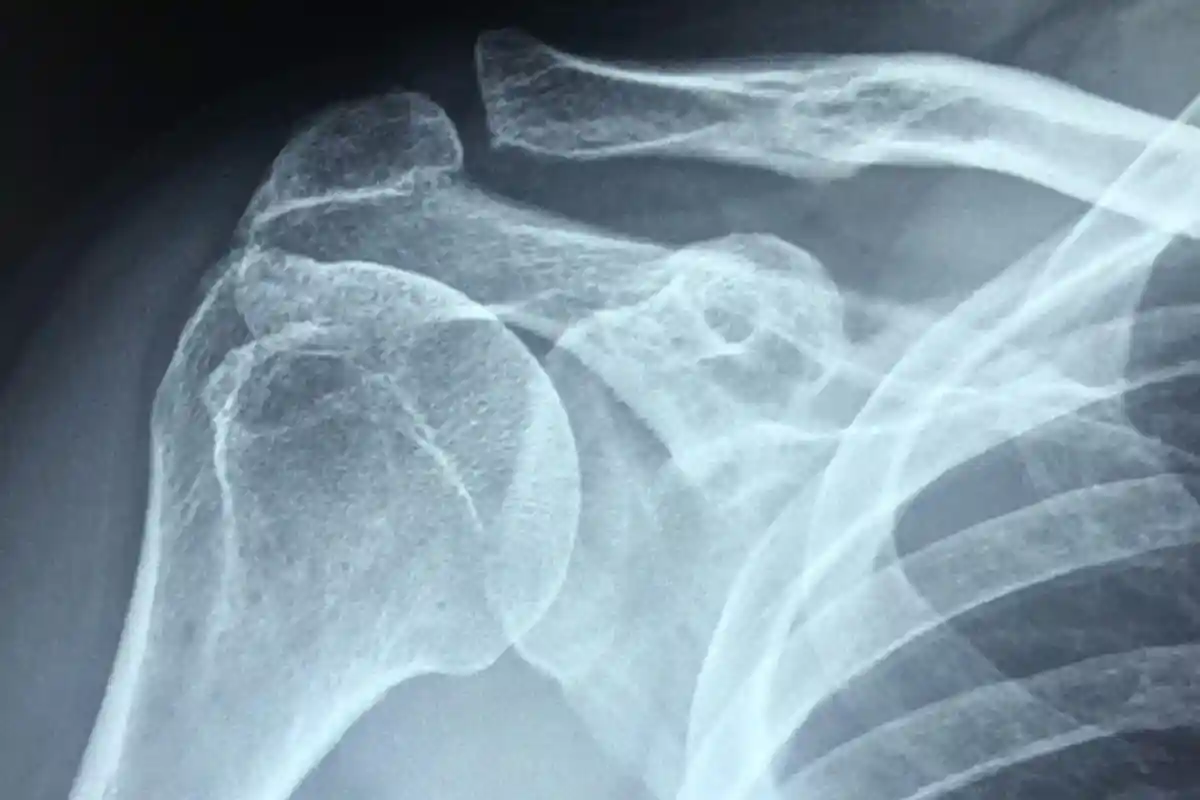

Звуження плечового суглоба може викликати сильний біль. Як проявляється синдром порушення та як його лікувати?

Імбінг-синдром плечового суглоба: Чому біль і нерухомість трапляються в плечі

Біль і нерухомість в плечі значно обмежують рух і ускладнюють повсякденне життя. Запалення або травма не завжди є причиною, повідомляє t -online.de. Іноді винна синдром плечового суглоба.